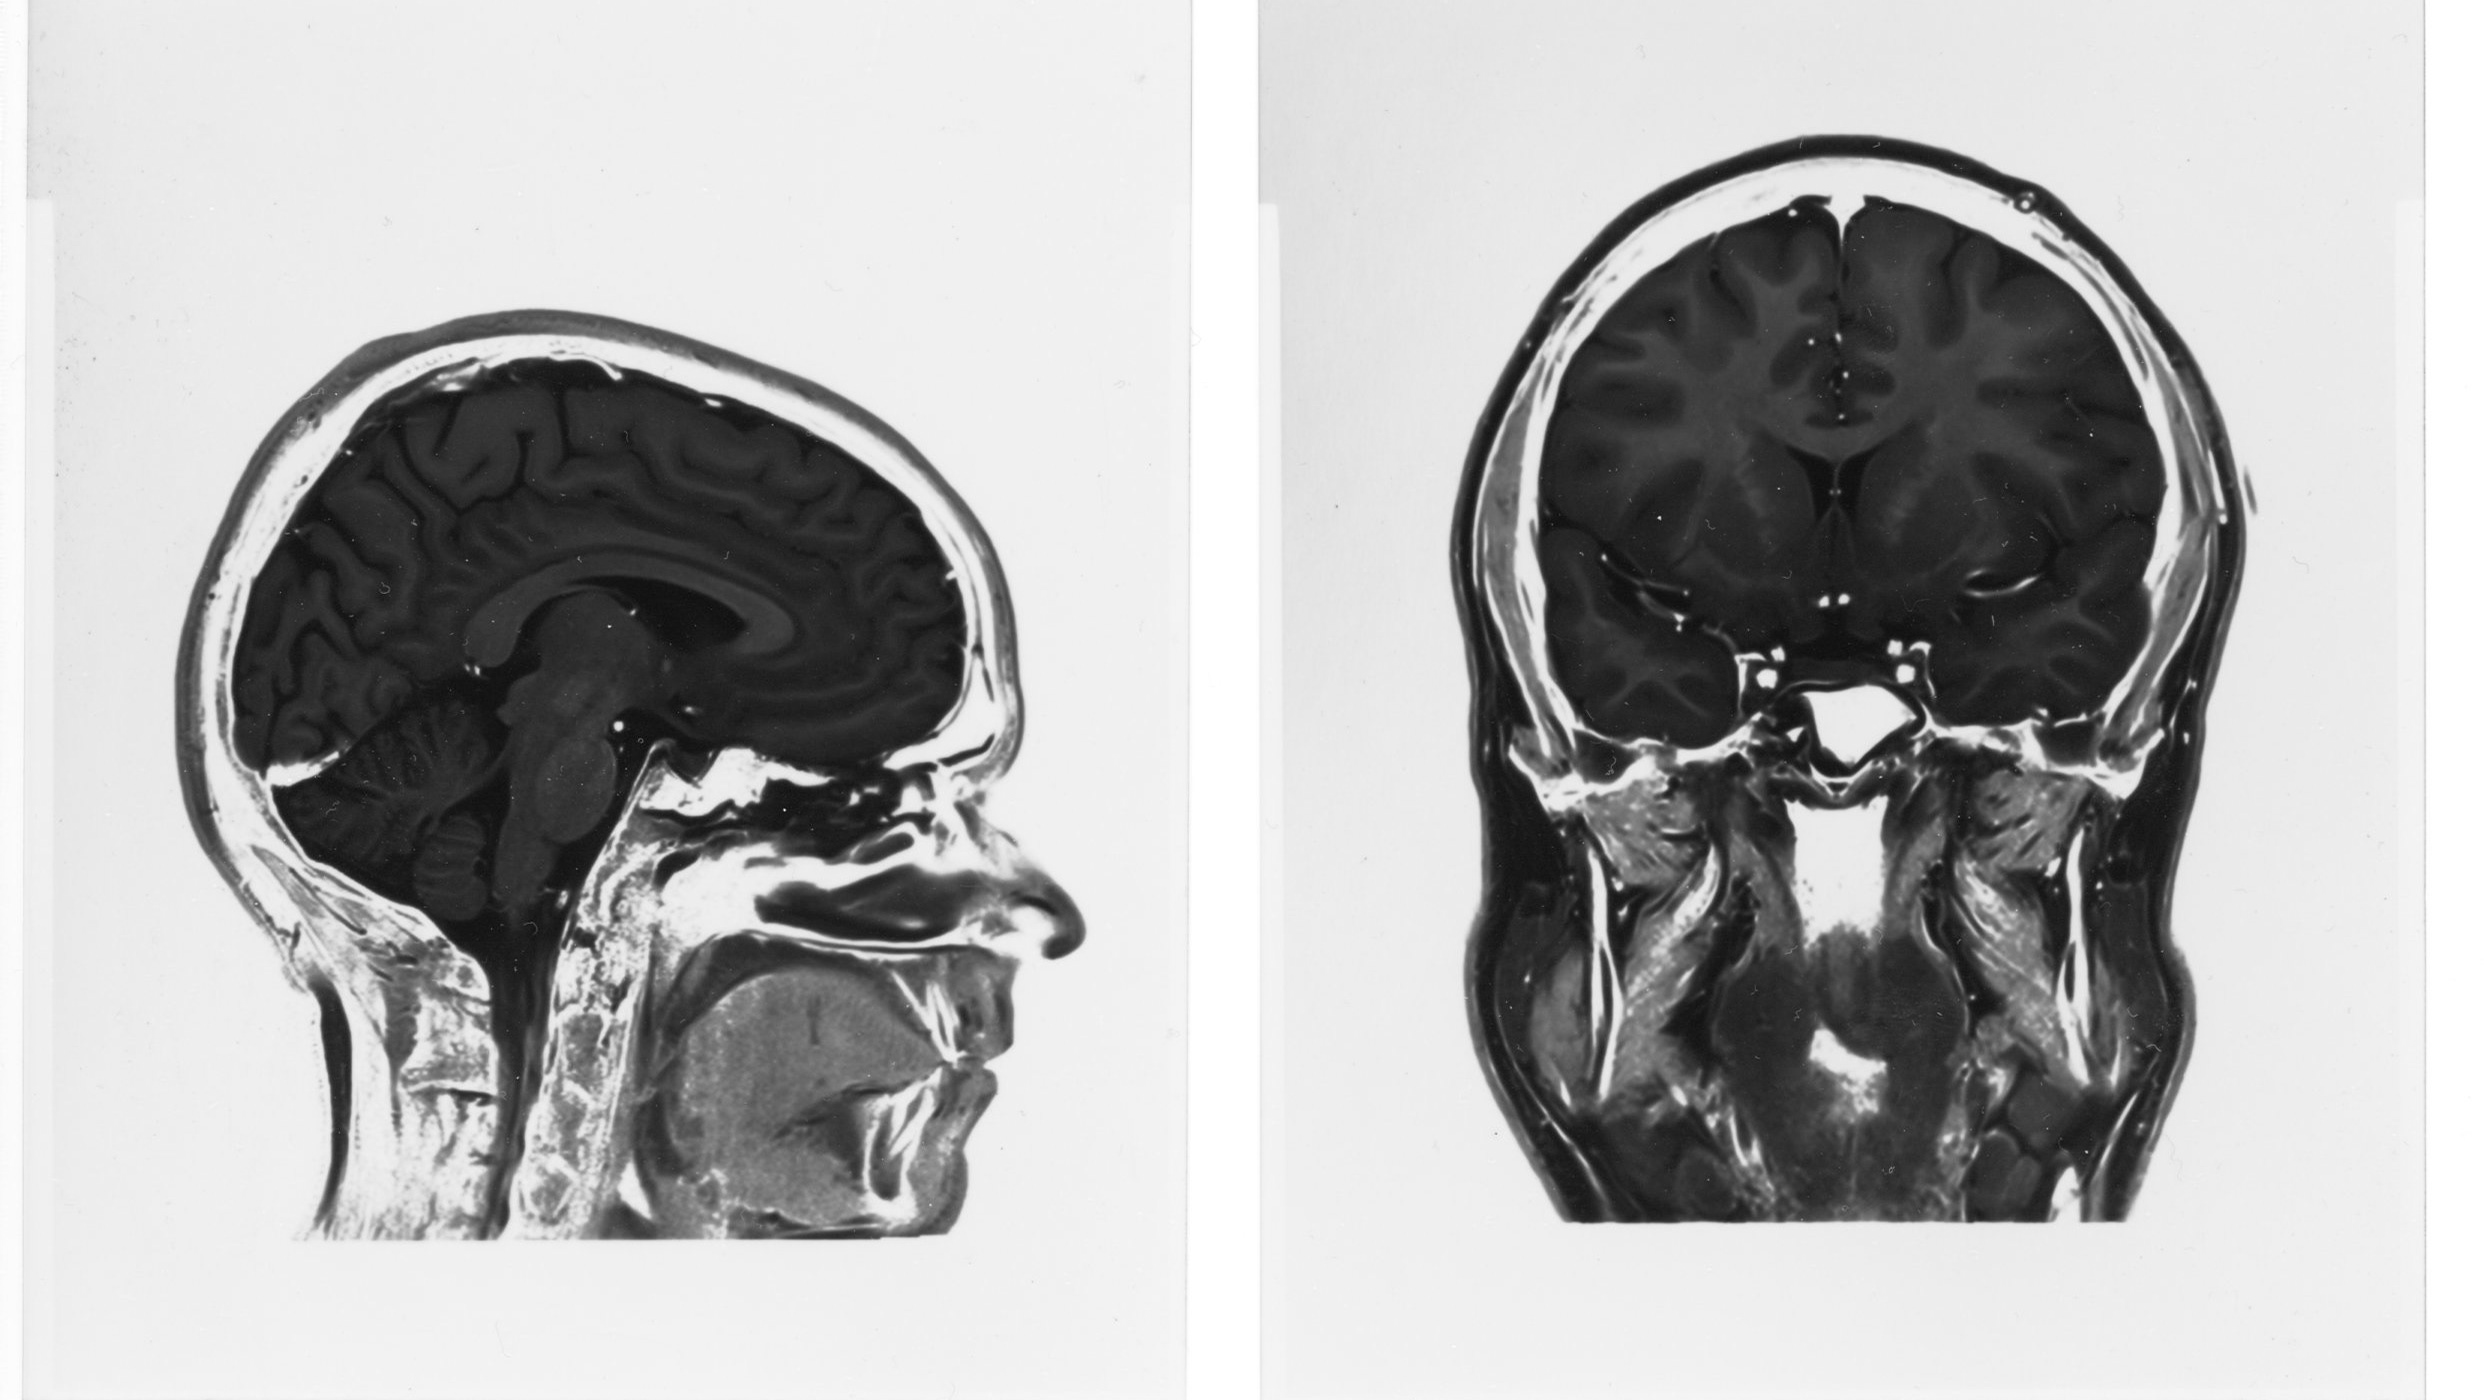

Hjernen er deg!